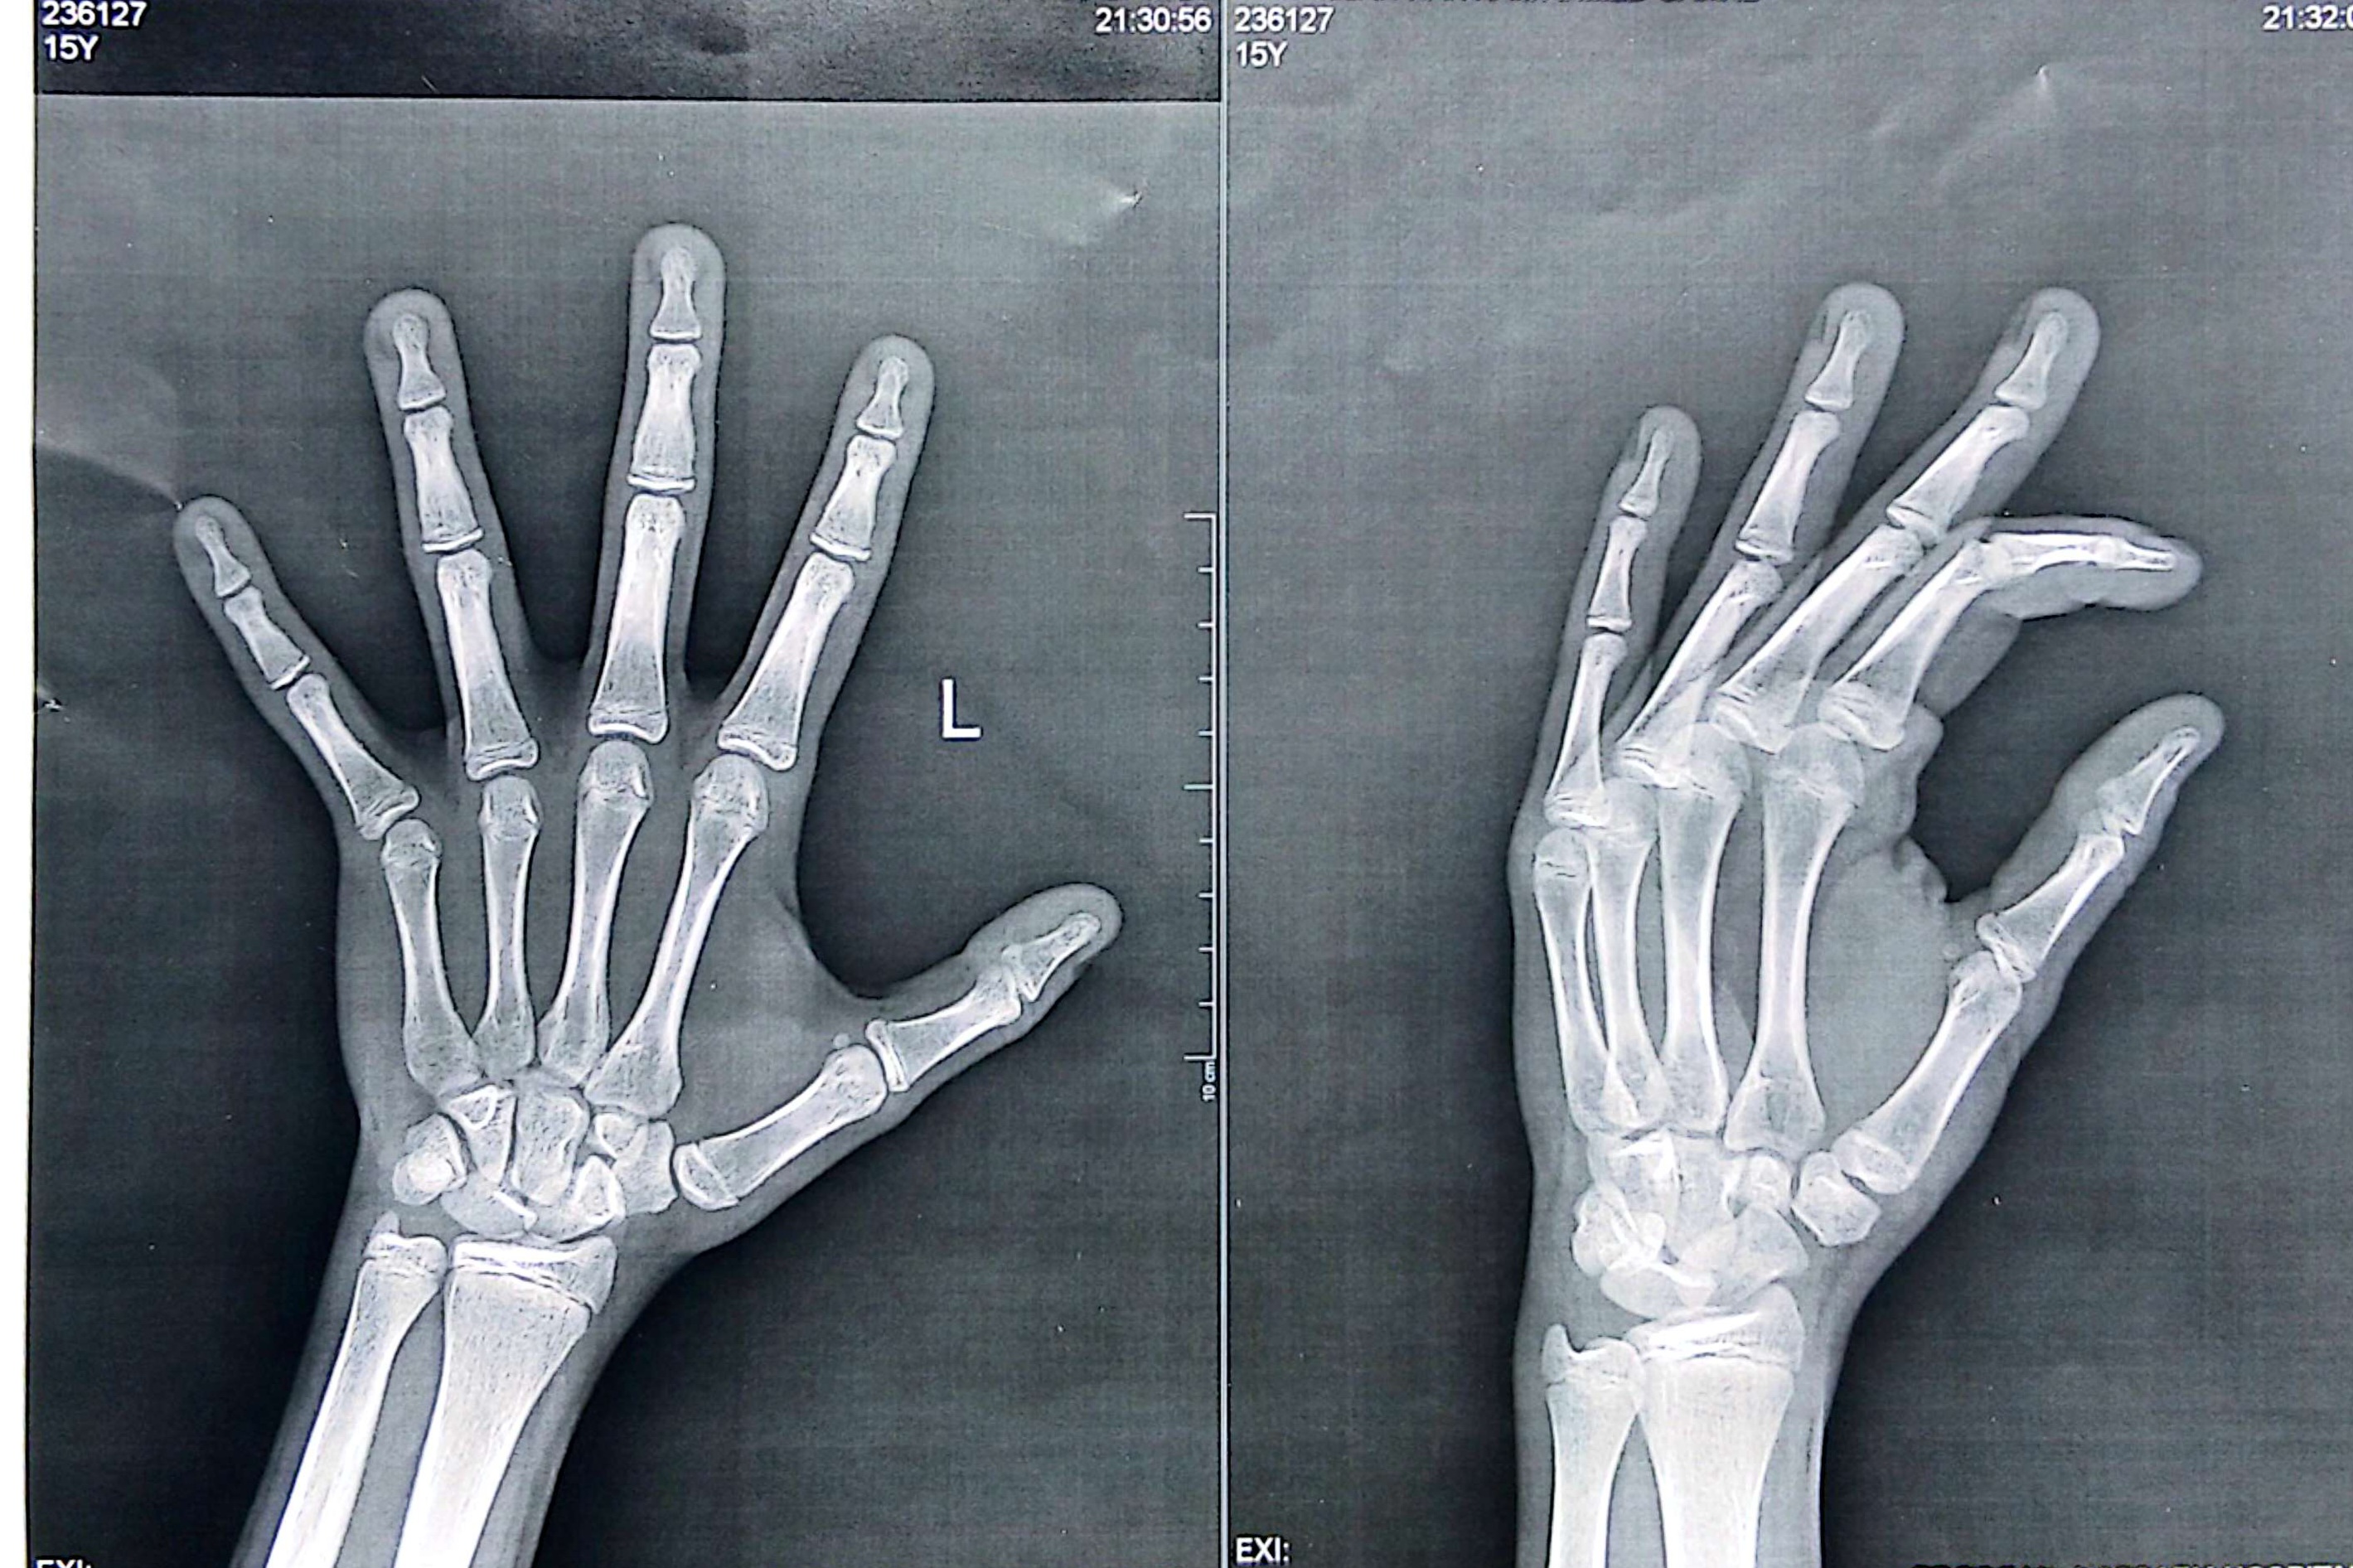

Yes he said 15Didn't your radiologist interpret it?

Then it's 15Yes he said 15

Idk man, probably 15 years and 5 months